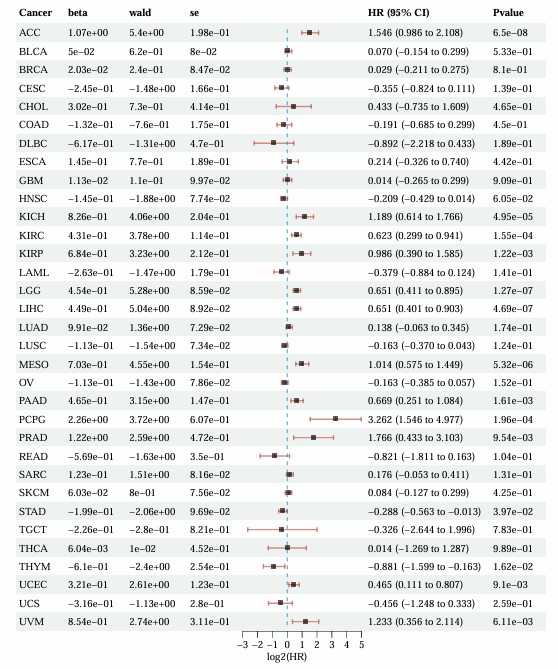

3.6. EZH2 expression across multiple cancer types

To determine the prognostic importance of EZH2 in multiple cancers, we analyzed TCGA data to measure EZH2 mRNA expression in diverse tumor tissues. A total of 36 cancer types and 10,228 samples were analyzed. EZH2 mRNA expression was found to influence prognosis in several cancers, including ACC, KIRP, KICH, LGG, PADD, KIRC, PRAD, UCEC, PCPG, LIHC and UVM (Figure 10). A forest plot, which presents the results of univariate Cox regression for EZH2 in multiple cancers, showed significant associations with p-values, hazard ratios (HR), confidence intervals (CIs), and β-values. These findings suggest that high EZH2 expression is a common feature across various tumors, highlighting its potential as a valuable therapeutic target.